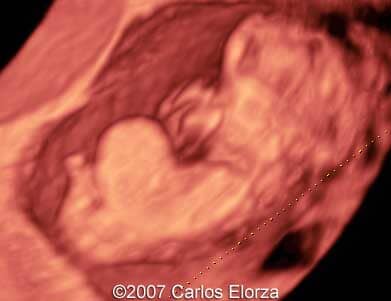

38-year-old woman (G3, P2)Ā presented in our department at 10th week of pregnancy. Ultrasound examination discovered striking nuchal edema and omphalocele with liver"s exenteration. A chorionic biopsy revealed trisomy 13. Here are someĀ images that we obtained.